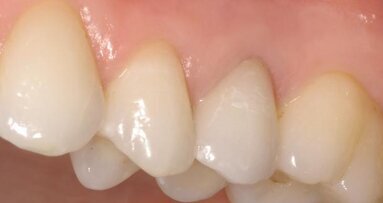

Fig. 21: After placement of the restoration and removal of excess adhesive cement and polishing of the margins and the surface.

Fig. 22: After polishing of the occlusal surface. The gingivae had been injured and needed to heal.

The endodontic retreatment and endocrown restoration of a badly damaged molar were carried out in a single clinical session. Postoperative clinical photographs and radiographs verified the results of the treatment: the molar recovered its anatomical forms and thus its function.

The endocrown restoration and the build-up material occupied the enlarged pulp chamber completely; the access to the root canals was thus closed hermetically. The margins of the endocrown also showed an adequate seal. The tight seal of the restoration will play a crucial role in the long-term results of the endodontic treatment.